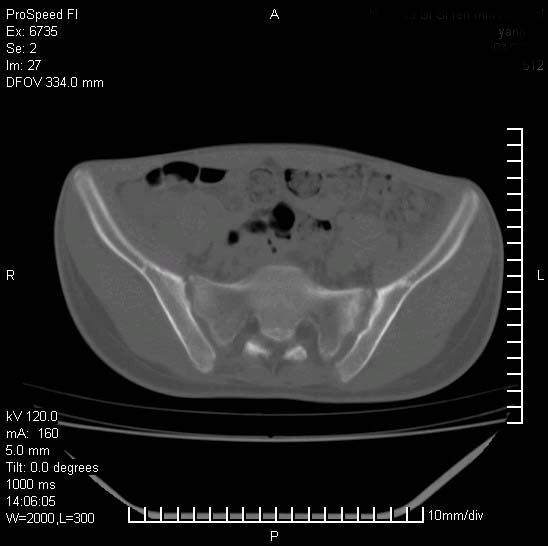

患者自诉胯部疼痛两年余,在当地服用中药,半月前至本院考虑骶髂关节结核,给予抗痨治疗。现发展至右下肢疼痛明显,活动受限,以膝关节处明显,拍膝关节平片无明显异常。

两侧骶骼关节改变,考虑强直性脊炎

左侧骶髂关节面限局性骨破坏,边缘硬化关节腔见钙化物;不出外tb

右侧骶髂关节也有类似改变,只是较左侧轻,首先考虑强直性脊柱炎,不除外结核,建议作hla-b27检查。

典型强脊炎改变,髋关节亦有累及

符合强直性脊柱炎表现。